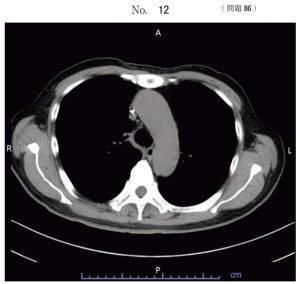

午後/問題86

胸部単純 CT 像(別冊No. 12)を別に示す。

カテーテルが挿入されている部位はどれか。

1.奇静脈

2.上大静脈

3.大動脈弓

4.上行大動脈

5.右鎖骨下動脈

答え

2